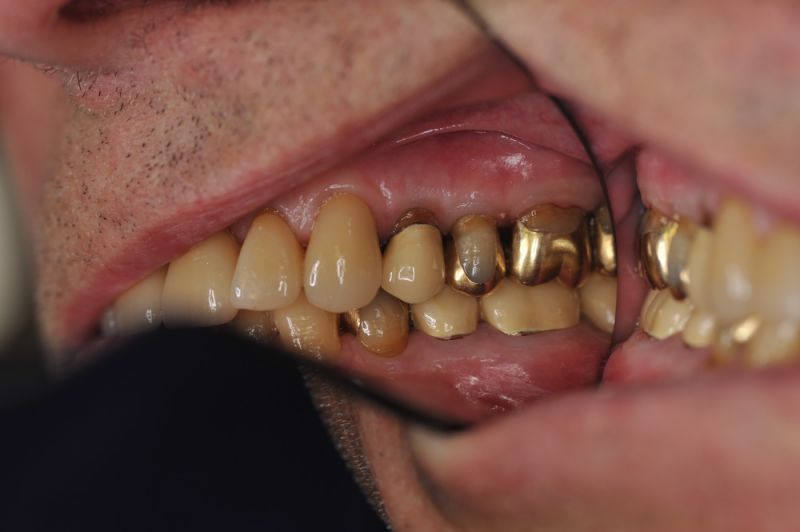

Rekonstruierter Kieler Patient im Recall

Dem Patienten geht es dental gesehen gut.

Die funktionstherapeutische Rekonstruktion befindet sich seit 17 Jahren im Munde des Patienten.

Gemeinsam ist man der Auffassung, dass sich heute zum Glück auszahlt, dass man beizeiten die Fundamente im Mund geschaffen hat, von denen der Patient heute im Alter zehrt.